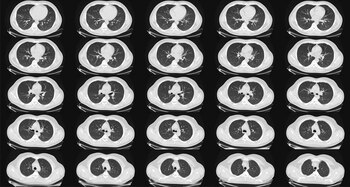

El uso de radiografías de tórax para detectar el cáncer de pulmón se abandonó en gran medida hace décadas porque no pudieron encontrar la enfermedad lo suficientemente temprano como para ser útil. Las tomografías computarizadas, llamadas tomografías computarizadas de dosis baja, porque involucran una cantidad relativamente pequeña de radiación, cuestan alrededor de USD 300. Se aconseja a los pacientes que dejen de hacerse los exámenes de detección una vez que no hayan fumado durante 15 años, o si desarrollan problemas de salud que acortarían sustancialmente su esperanza de vida o no les permitirían someterse a una cirugía de pulmón si fuera necesario.